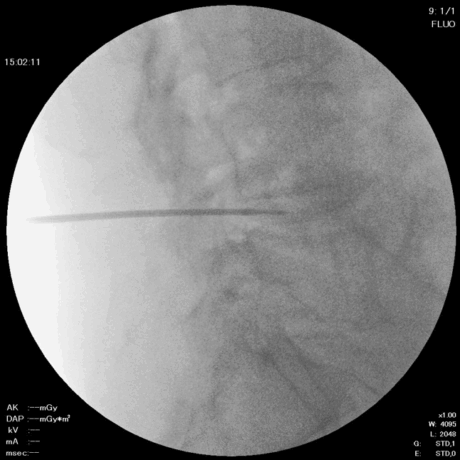

1. 麻酔と穿刺

椎間板造影と同じように椎間板に穿刺し、局所麻酔を行います。

頚椎では前方から、腰椎では後方から、神経を圧迫している部位にアプローチします。

2. ニードル留置

直径約2mmのニードルを椎間板に留置します。